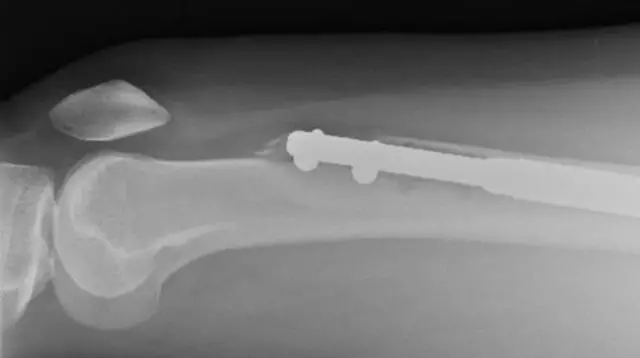

ด้วยการผ่าตัดนี้ ความเจ็บปวดอย่างนั้นเป็นเรื่องที่คาดว่าจะเกิดขึ้นอยู่แล้ว ส่วนในระหว่างการผ่าตัด กระดูกขาแยกจะถูกออกเป็นสองส่วนและมีแท่งโลหะถูกผ่าตัดนำไปใส่ไว้ข้างใน

แท่งโลหะค่อย ๆ ยืดออกเพื่อเพิ่มความยาวและดึงกระดูกทั้งสองซีกออกจากกัน กระบวนการนี้มีวัตถุประสงค์เพื่อเพิ่มความสูงของผู้ป่วย กระดูกที่แยกกันทั้งสองส่วนควรจะค่อย ๆ รักษาตัวเองและเชื่อมต่อเข้าหากันเพื่อเติมเต็มช่องว่างนั้น

ต่อมาเอเลนจึงเข้าไปพบหมอเพื่อทำการสแกน ซึ่งเป็นการยืนยันความกลัวของเธอ แกนเหล็กที่ขาซ้ายของเธอหักผ่านกระดูกโคนขาหรือกระดูกต้นขาของเธอ ซึ่งถือเป็นกระดูกที่แข็งแรงที่สุดในร่างกายมนุษย์ เธอเสียใจมาก แต่เธอบอกว่า เธอได้รับความมั่นใจจาก ดร.กีเชต์

อีก 6 สัปดาห์ต่อมา การสแกนขาขวาของเธอแสดงให้เห็นการเจริญเติบโตของกระดูกที่น่ากังวลใจ ขณะที่กระดูกโคนขาของเธอกลับเป็นกระดูกสองชิ้นที่ยึดเข้าด้วยกันด้วยแท่งโลหะ